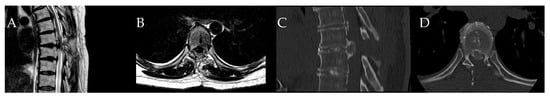

- Yuan, L.; Chen, Z.; Liu, Z.; Li, W.; Sun, C.; Liu, X. Clinical and radiographic features of adult calcified thoracic disc herniation: A retrospective analysis of 31 cases. Eur. Spine J. 2023, 32, 2387–2395. [Google Scholar] [CrossRef] [PubMed]